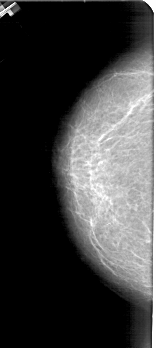

A_1433_1.LEFT_CC

LEFT_CC LINES 4861 PIXELS_PER_LINE 2176 BITS_PER_PIXEL 12 RESOLUTION 43.5 NON_OVERLAY